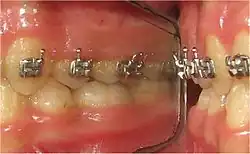

- Interpositions linguales : depuis la percée de la gencive, les dents définitives poursuivent une éruption passive jusqu'à toute occlusion (contact). Quelle occlusion ? Non celle avec la dent antagoniste (déglutition physiologique), mais bien celle des 1500 à 2000 pressions verticales quotidiennes de la langue sur les arcades dentaires. Il s'ensuit un ralentissement, suivi d'un arrêt prématuré de l'éruption de la dent définitive (Fig.1 et 2).

Les interpositions linguales induisent l'arrêt prématuré de l'éruption passive des dents dans la cavité buccale. L'interception consiste à créer le contact dento-dentaire antagoniste par réduction brutale d'un Espace libre trop grand. Ce contact entre des dents antagonsite stimule les mécanorécepteurs de la proprioception desmodontale (sensibilité tactile inconsciente[16],[17],[46],[47]).

- Dès le plus jeune âge (enfant, adolescent), mise en place d'un réducteur d'espace interocclusal de repos, ou REIOR[45], sur les molaires supérieures (Fig.13), gauche et droite : deux molaires lactéales (4 à 8 ans) ou deux molaires permanentes (à partir de 10 ans).

- Toutes les dents permanentes, « libres d'un REIOR », se retrouvent « suspendues dans le vide » : elles reprennent une éruption dento-alvéolaire passive. Ceci confirme le ralentissement et l'arrêt du processus d'éruption buccale par les pressions verticales de la langue lors de ses 1500 à 2000 interpositions quotidiennes entre les arcades dentaires (déglutition infantile, déglutition atypique).